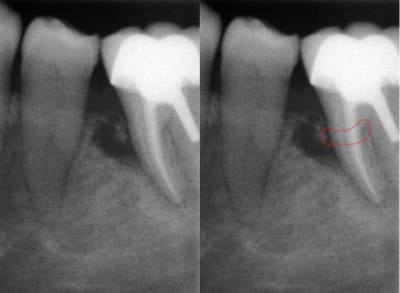

J'ai réalisé une endo sur la 36 début 2015 afin de réaliser un tfm et une coiffe ccm.

J'ai posé cette dernière il y a environ 3 mois et aujourd'hui j'ai revu la patiente qui se plaint d'une gêne à la gencive sans vraiment parler de douleur;

Je vous fais passer la radio qui montre une image au niveau du septum 35 36 et je suis vraiment étonné qu'en l'espace de si peu de temps je puisse avoir une telle lésion.

D'après vous est-ce un problème endo, paro (j'ai bien nettoyé l'espace aujourd'hui sous AL afin de vérifier l'absence d'un fragment de ciment de scellement mais rien de particulier).

> La fracture parait s'imposer comme une évidence.

Peut-être, mais typiquement les fractures( et fêlures) donnent des lésions en "doigt de gant" : elargissement au niveau desmodontal remontant jusqu'à la surface, et ce n'est pas le cas ici. En plus le délais semble court, pour une telle lésion consécutive à fracture, et pas de douleur à la pression(?).

Merci pour vos avis,en grossissant la radio on peut effectivement penser à une fracture de la racine.Ce n'est pourtant pas la racine qui supporte le tenon.